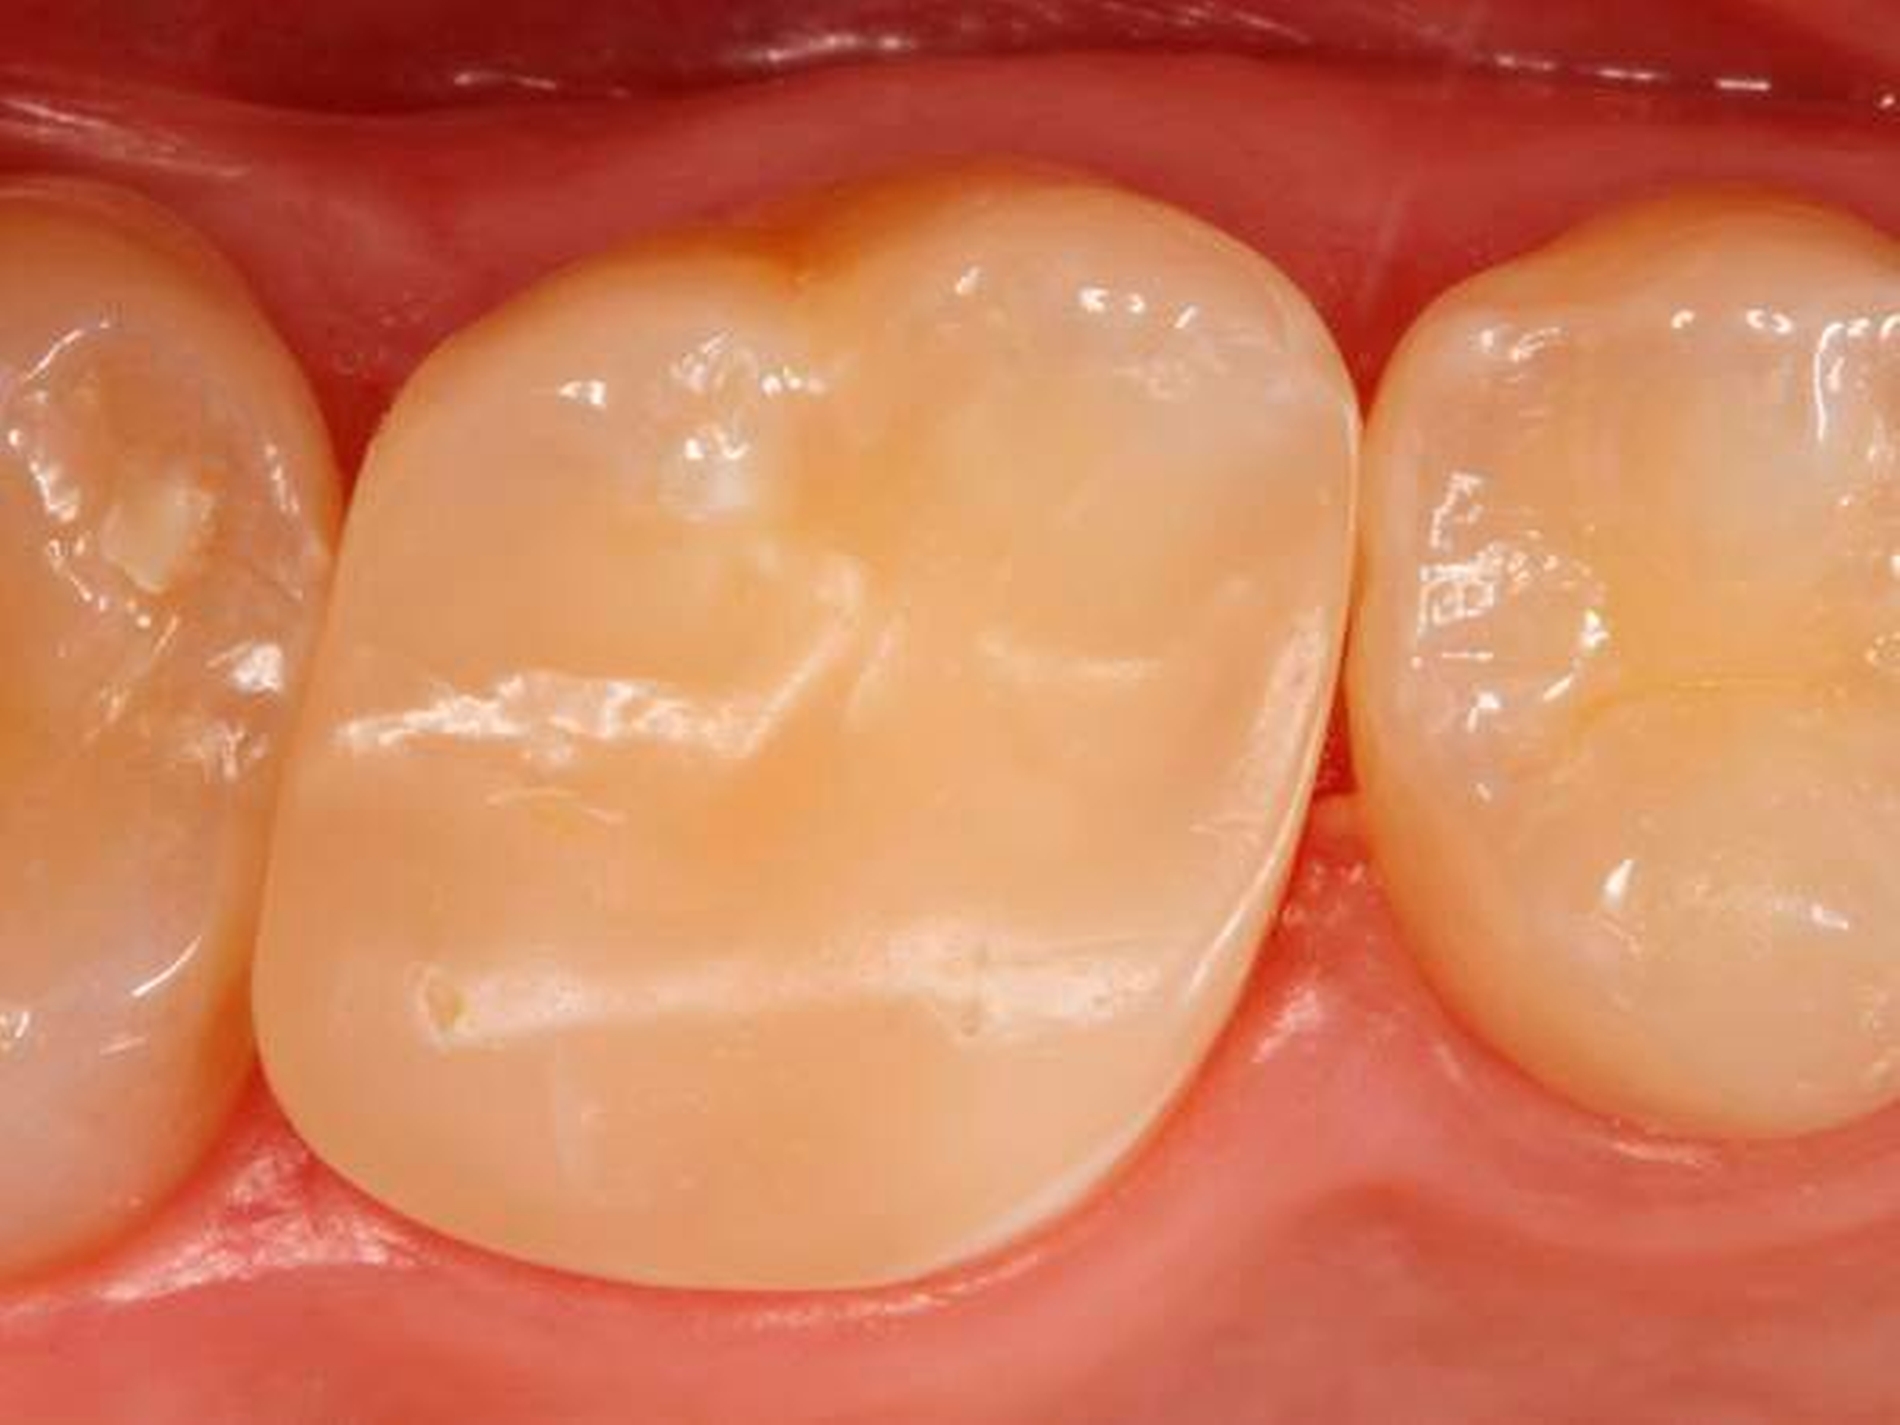

Abbildung 4 zeigt die fertig ausgearbeitete und polierte Restauration unmittelbar nach Behandlungsabschluss, Abbildung 5 bei einer weiteren Kontrolle nach einem Jahr: Der Zahn war inzwischen komplett beschwerdefrei, zeigte im Sensibilitätstest vergleichbare Reaktionen wie die Nachbarzähne. Die Oberfläche erschien allerdings etwas matt, was aber durch eine kurze Nachpolitur (Sof-Lex Polierrad „sehr fein“, 3M) wieder in eine hochglänzende Oberfläche verwandelt werden konnte (Abb. 6). Die Restauration integrierte sich ästhetisch und funktionell optimal in die umgebende Zahnhartsubstanz.